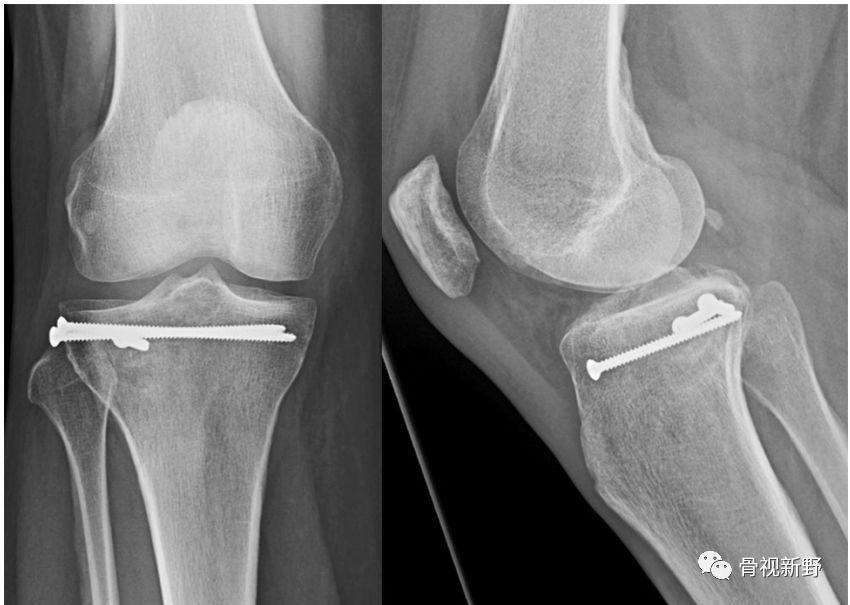

"平行螺钉”固定,是由Schatzker于1979年提出的胫骨平台经皮、微创固定理念,适合Schatzker I-III型胫骨平台骨折的固定,特别是Schatzker I型(单纯劈裂)。平行固定可用2枚半螺纹拉力螺钉或皮质骨螺钉(“排钉”)在软骨下骨进行骨折的水平固定。

Moran E(2017)对传统“三角螺钉固定”技术进行改良,将第3枚防滑螺钉的方向朝向拉力螺钉的尖端而形成螺钉尖端汇聚,螺钉分布在侧位呈倒“品”字形进钉;正位X光片(或透视)像上螺钉呈三角形分布(如下图)。

具体固定方法:2枚带垫片、相互平行的6.5 mm半螺纹拉力螺钉(相距15 mm)垂直骨折线在距关节面7mm以下打入软骨下骨。第3枚三角固定螺钉选择带垫片的全螺纹6.5mm 松质骨螺钉,从骨折块尖端呈30°角(正位透视)打入,螺钉尖部与2枚拉力螺钉尖部汇合,第3枚螺钉起防滑、支持作用( Moran E 2017)。

51ys, F。胫骨外侧平台骨折(Schatzker II型)

透视监测下,经皮顶棒复位塌陷的关节面,经皮在软骨下骨内打入2枚3.5-mm皮质骨螺钉作为排钉。(顶棒)骨隧道内植入8 mm *35 mm的界面螺钉(施乐辉)支撑复位的关节面。

2枚排钉和一枚前-后方向的栅栏螺钉相垂直固定。加用栅栏螺钉的目的是防止排钉对松质骨的切割。

术后6周非负重的运动,之后6周循序渐进地部分负重;术后 12月,骨折愈合;未见骨折移位、再塌陷;关节面平整,无高度丢失。